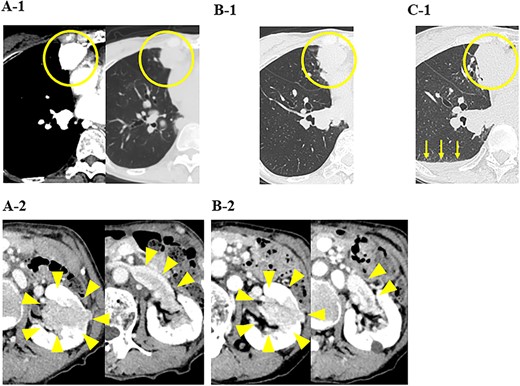

A79-year-old female underwent right thyroid lobe resection and cervical lymph node dissection for PTC at a previous hospital. Five years after the initial surgery, follow-up computed tomography (CT) revealed multiple masses in both lung fields, with the largest tumors in the middle lobe of the right lung measuring 2.6 cm. These tumors previously showed a high signal intensity in the early phase of contrast-enhanced CT (Fig. 1A-1). A mass of ~4 cm was detected in the left kidney with a tumor plug in the left renal vein (Fig. 1A-2). From the CT findings and clinical course, primary renal cell carcinoma (RCC) with multiple pulmonary metastases were strongly suspected, and the administration of nivolumab and ipilimumab was initiated. Five months later, CT showed increases in the sizes of the pulmonary tumors (Fig. 1B-1) and a decrease in the size of the renal tumor (Fig. 1B-2).

CT images of the chest and abdomen; (A) at the start of the administration of nivolumab and ipilimumab, CT showed multiple masses in both lung fields and a mass in the left kidney with a tumor plug in the left renal vein, and (B) 5 months after the administration of nivolumab and ipilimumab, CT showed increases in the sizes of the pulmonary tumors and a decrease in the size of the renal tumor, and (C) 6 months after the administration of nivolumab and ipilimumab, CT showed increases in the sizes of the pulmonary tumors and pleural effusion (yellow arrows).

In our hospital, CT-guided core needle biopsy was performed on the pulmonary mass of the right middle lobe. At the time of biopsy, which was performed ~1 month after the last CT scan, increases in the sizes of the pulmonary tumors (tumor growth rate of pulmonary tumors; 29%) (Fig. 1C-1) and pleural effusion (Fig. 1B-1) were noted on CT. A pathological examination revealed that the tumor formed a papillary structure and the lumen was filled with colloids. Since immunohistochemistry results were positive for Tg (Fig. 2), the mass was considered to be pulmonary metastasis of PTC. The patient was diagnosed with pulmonary metastases of PTC, and the administration of lenvatinib was initiated. Since nivolumab and ipilimumab were administered until just before the initiation of lenvatinib, the starting dose of lenvatinib was 8 mg/day. Fatigue (grade 2) and skin disorders (grade 2) developed 3 weeks after the initiation of lenvatinib, and thus, the dose was reduced to 4 mg/day. Three weeks after the dose reduction, hypertension (grade 2) was observed. The patient was administered olmesartan medoxomil, which returned blood pressure to normal.